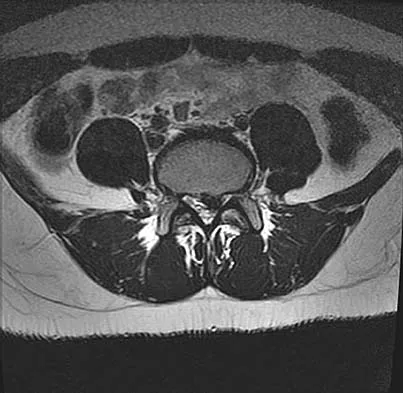

A patient has right shoulder pain. Figure 1a shows a gadolinium-enhanced transverse MRI scan at the level of the coracoid. Figure 1b shows an arthroscopic view of the anterior structures from a posterior portal. These images reveal which of the following findings?

The area shown in the arthroscopic view and MRI scan is referred to as a Buford complex and represents a normal labral variant. It consists of a thickened, cord-like middle glenohumeral ligament, a superior labral attachment of the middle glenohumeral ligament just anterior to the biceps tendon, and absence of the anterosuperior labrum. This combination of findings can be confusing and may simulate labral pathology. Mistaken repair of the lesion back to the glenoid rim can result in significant loss of external rotation. A Bankart lesion would be located at the inferior anterior glenoid rim. The subscapularis is seen anterior to the labrum. Normal variations that occur in the anterosuperior labrum can simulate pathology. Gusmer PB, Potter HG, Schatz JA, et al: Labral injuries: Accuracy of detection with unenhanced MR imaging of the shoulder. Radiology 1996;200:519-524. Griffin LY (ed): Orthopaedic Knowledge Update: Sports Medicine. Rosemont, IL, American Academy of Orthopaedic Surgeons, 1994, pp 47-63.

- Williams MM, Snyder SJ, Buford D Jr: The Buford complex: The "cord-like" middle glenohumeral ligament and absent anterosuperior labrum complex. A normal anatomic capsulolabral variant. Arthroscopy 1994;10:241-247.